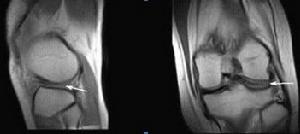

(2)MRI檢查:可發現髕骨軟骨的剝脫和潰瘍區

2.MRI檢查 可發現髕骨軟骨的剝脫和潰瘍區。